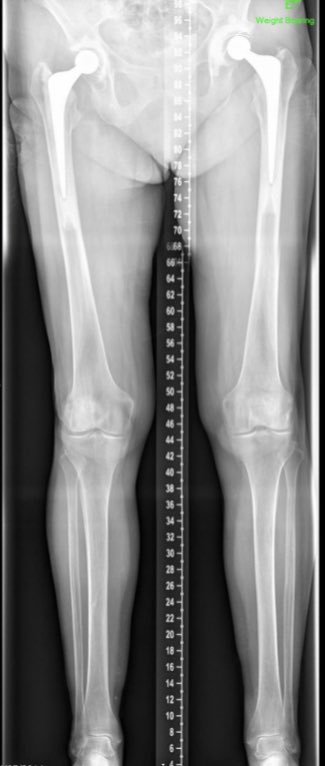

Leg length films really helpful for planning in many cases like this & with congenital proximal femoral deformity. The challenges in operating here are multiple

And here are the pre and post op films. Correction of length and offset. So far (several years) a stable hip and a delighted patient. Thankfully.